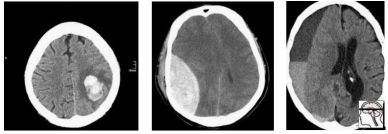

Now let’s sample this population to build our test set:

Randomly, we end up with mostly extra-axial (outside of the brain itself) bleeds. A model that performs well on this test will not necessarily work as well on real patients. In fact, you might expect a model that is really good at extra-axial bleeds at the expense of intra-cerebral bleeds to win.